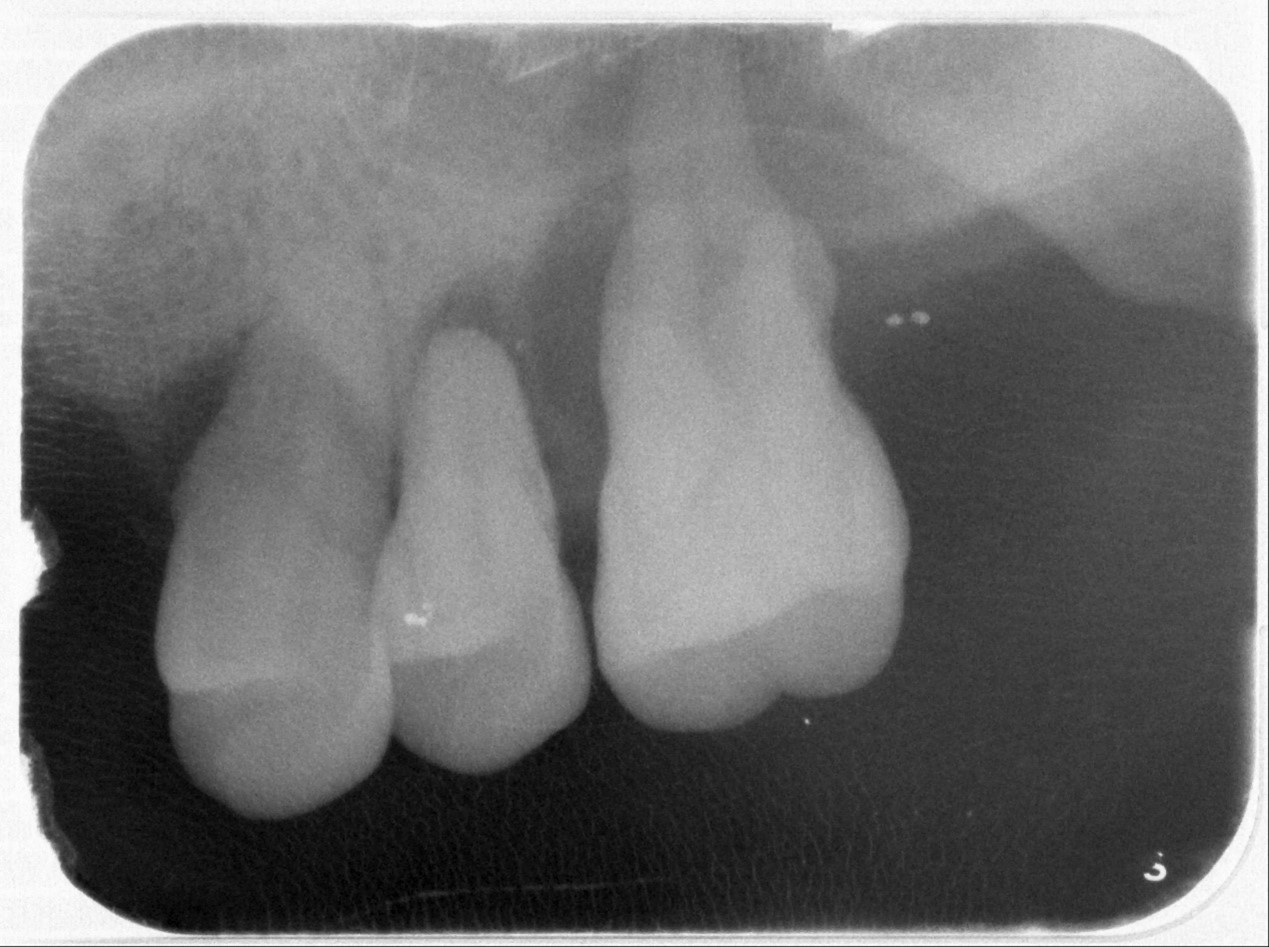

北榮桃園分院牙科主任王碩表示,臨床上常見牙周炎症狀包括牙齦易出血、牙齦紅腫、口臭、牙齦退縮、牙根敏感與牙齒動搖等。牙周病治療前,醫師會先進行完整評估,包含量測全口牙周囊袋深度、出血點、齒齦退縮量、牙根分岔處的狀態、牙齒動搖度等指標,並搭配影像檢查。牙周病於放射線檢查,常可見水平式齒槽骨喪失,或呈狹角向根尖延伸的垂直(角形)骨缺損;骨缺損的深度與形態,不僅反映病情嚴重性,更影響後續是否能採行再生手術治療。